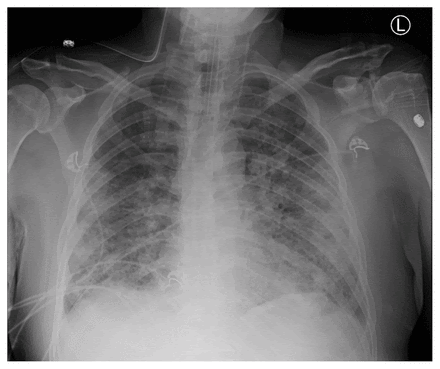

Crispin la valiente / Getty Images